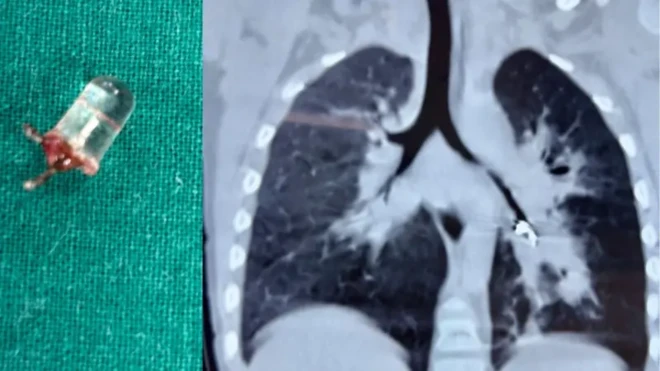

،تصویر کا ذریعہFGED

کارلوس آریلانو کے مطابق ’مجھے شکوک و شبہات تھے، لہٰذا میں نے ان کی جانچ کرنے کا فیصلہ کیا اور دیکھا کہ لڑکی کے امپلانٹس ہیں۔‘

چنانچہ 21 ستمبر کو انھوں نے پراسیکیوٹر کے دفتر رابطہ کر کے پوسٹ مارٹم کرنے کی درخواست کی۔